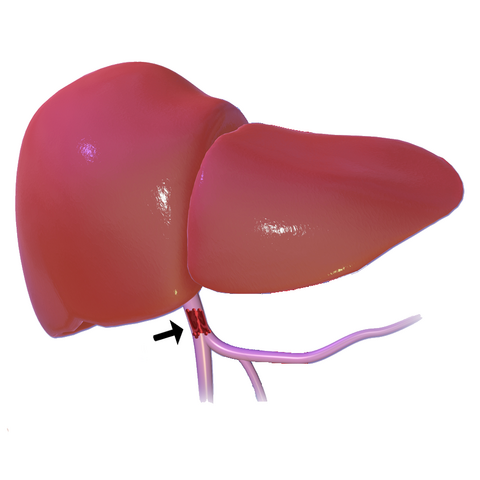

В последние годы в социальных сетях и блогах все чаще встречается необычное явление, известное как “Печень фото”. Этот термин относится к художественному стилю, при котором фотографии печени человека становятся объектом эстетического восприятия и даже искусства. Такие изображения, часто с высоким разрешением и детальной проработкой текстур, привлекают внимание не только медиков и исследователей, но и широкой публики, вызывая удивление и восхищение своей красотой и уникальностью.

Печень фото